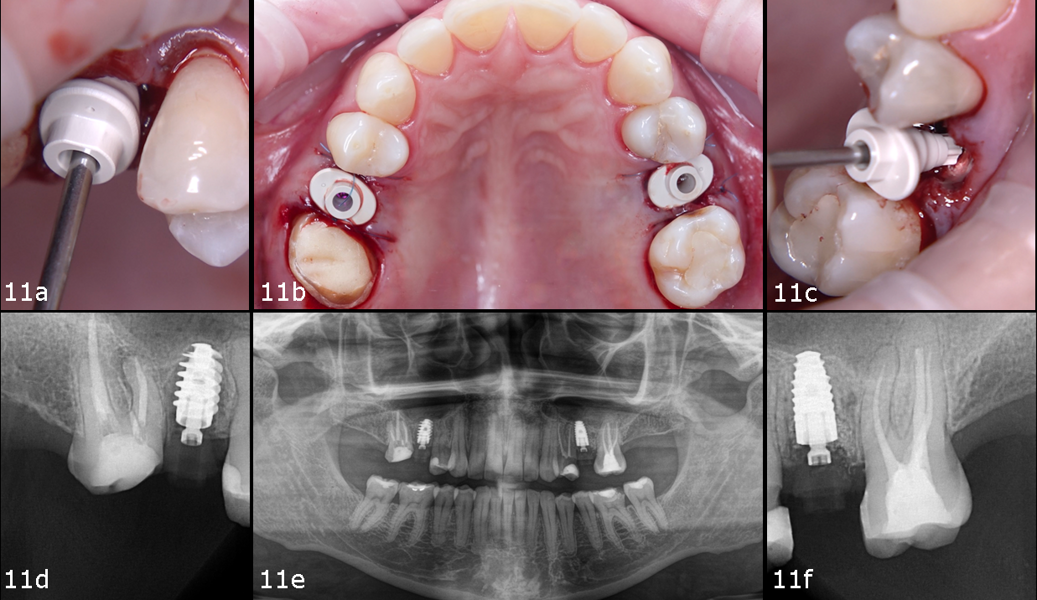

To preserve the ridge contour over time, cerabone plus was hydrated according to the manufacturer’s instructions and placed into the buccal gap at site #25 (Figs. 10a–f). Both sites received healing abutments and were sutured using mesial and distal single interrupted sutures to ensure soft-tissue stability during the healing phase (Figs. 11a–f & Figs. 12a–d). The patient received postoperative instructions along with an analgesic prescription and was scheduled for suture removal after two weeks.